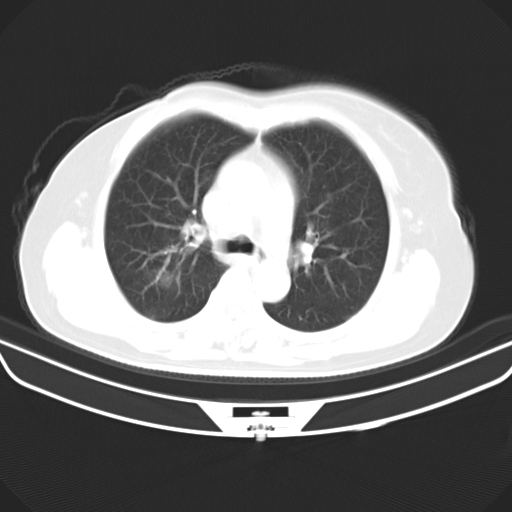

以下是引用zjzjr在2007-3-23 13:28:00的发言:[br]右肺上叶后段可见一结节状高密度影,可见毛刺征,胸膜凹陷征及血管导入征,纵隔内可见肿大淋巴结影.考虑右肺上叶周围型肺癌伴纵隔淋巴结转移.

以下是引用zjzjr在2007-3-23 13:28:00的发言:[br]右肺上叶后段可见一结节状高密度影,可见毛刺征,胸膜凹陷征及血管导入征,气管前腔静脉后可见肿大淋巴结影.考虑右肺上叶周围型肺癌伴纵隔淋巴结转移.